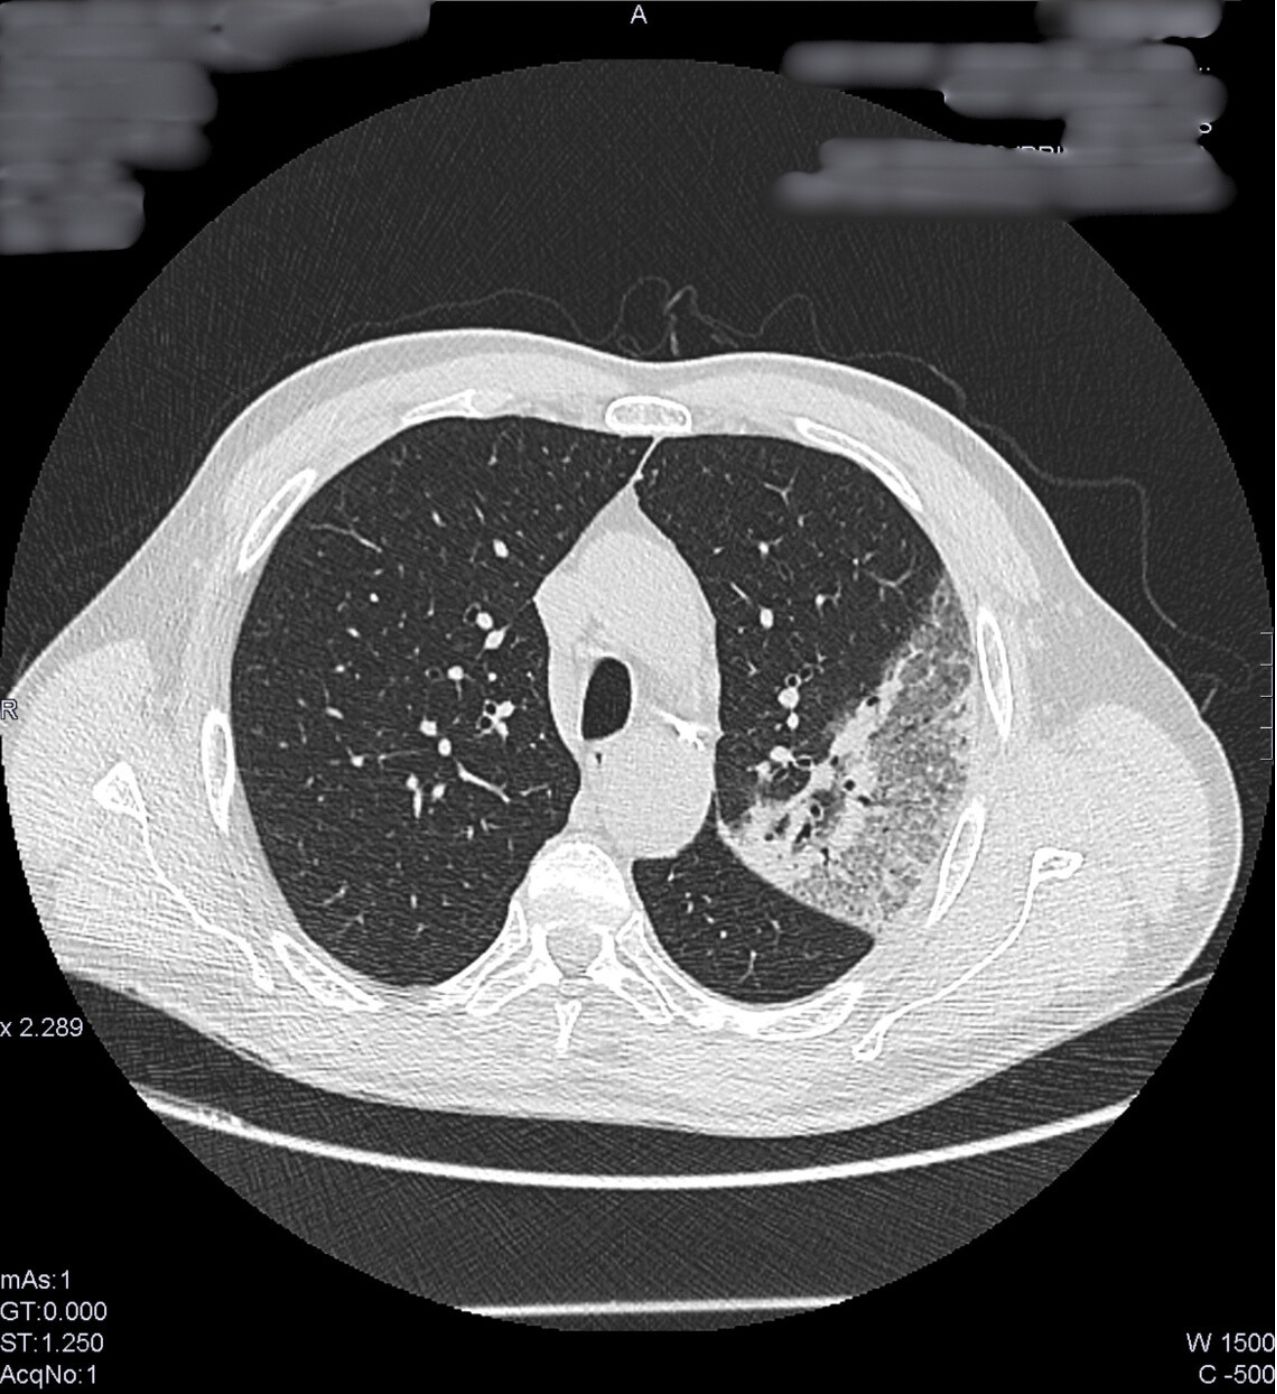

TC de tórax sin contraste intravenoso